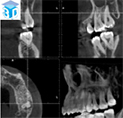

上図のような歯科用CTから得られる三次元的情報は、インプラント治療、歯周病治療、根管治療親知らずの抜歯など歯科治療のあらゆる分野での診断に必要不可欠なものとなってきています。詳しくはGCホームページをご覧ください。